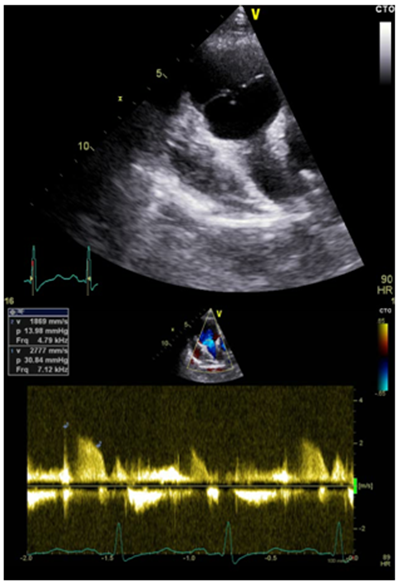

33 years old male patient, smoker, with a history of treated asthma , left posttraumatic pneumothorax with repeted pleurodesis, solved by surgery is admitted for dyspnea at rest, dry cough accentuated in clinostatism and cyanosis, symptoms that worsened two months before admission, onset two years ago. The clinical examination revealed a left latero-thoracic postsurgical scar, mixt cyanosis, rest dyspnea, dry cought, normal pulmonary auscultation, SpO2=97%, anterior chest pain, turgid jugular veins, tachycardia, BP=130/70mmHg, left parasternal continuous murmur of high intensity, accentuated by Valsalva maneuver, loud S 2 palpable in pulmonary area, systolic tricuspid murmur, no edemas, hepatomegaly and hepato-jugular reflux. Electrocardiogram (Figure 1) showed sinusal tachycardia, 120bpm, right bundle branch block, right axis deviation. The blood samples revealed myocardial and hepatic cytolyse, increased creatinine. On chest X-ray as showed in Figure 2 we found cardiomegalia, straight left middle cardiac arch, pulmonary stasis, latero-basal pachypleurites and left fissure inflamation. Performing the transthoracic ecocardiography (Figure 3a-3c) we noted normal LV systolic function, enlargement of the right cavities and pulmonary artery, mild mitral regurgitation, medium-mild pulmonary regurgitation, moderate functional tricuspidian regurgitation, noncoronary Valsalva sinus aneurysm ruptured into the RA with hemodynamic significant left to right shunt and mild pericardites. The contrast echocardiography found slow opacification of the right cavities without comunication between right and left cavities. During Valsalva maneuver on echocardiography air bubbles are visible into the right cavities with dissapearance after 10minutes of left lateral decubitus, during this event the patient`s dyspnea becomes more intense. The thoracic CT scan fails to find a broncho-vascular fistula. The transesophageal echocardiography better defines the communication without other congenital defects. Abdominal ultrasound reveales mild ascites and hepatosplenomegalia. He receives treatment with antialdosteronic and loop diuretic, unfractioned heparine, beta blockers , bronchodilator and intermitent oxygenoterapy. The patient is transferred for the surgical repair with good evolution and hemodynamic compensation. During surgery no other defects or fistulas were identified. On follow-up the patient was stable with mild pulmonary hypertension, one episode of atrial flutter and no signs of heart failure.1‒3

Figure 3c Tricuspid aorta, non-coronary sinus aneurysm communicating with the RA, left to right shunt; mild aortic regurgitation.